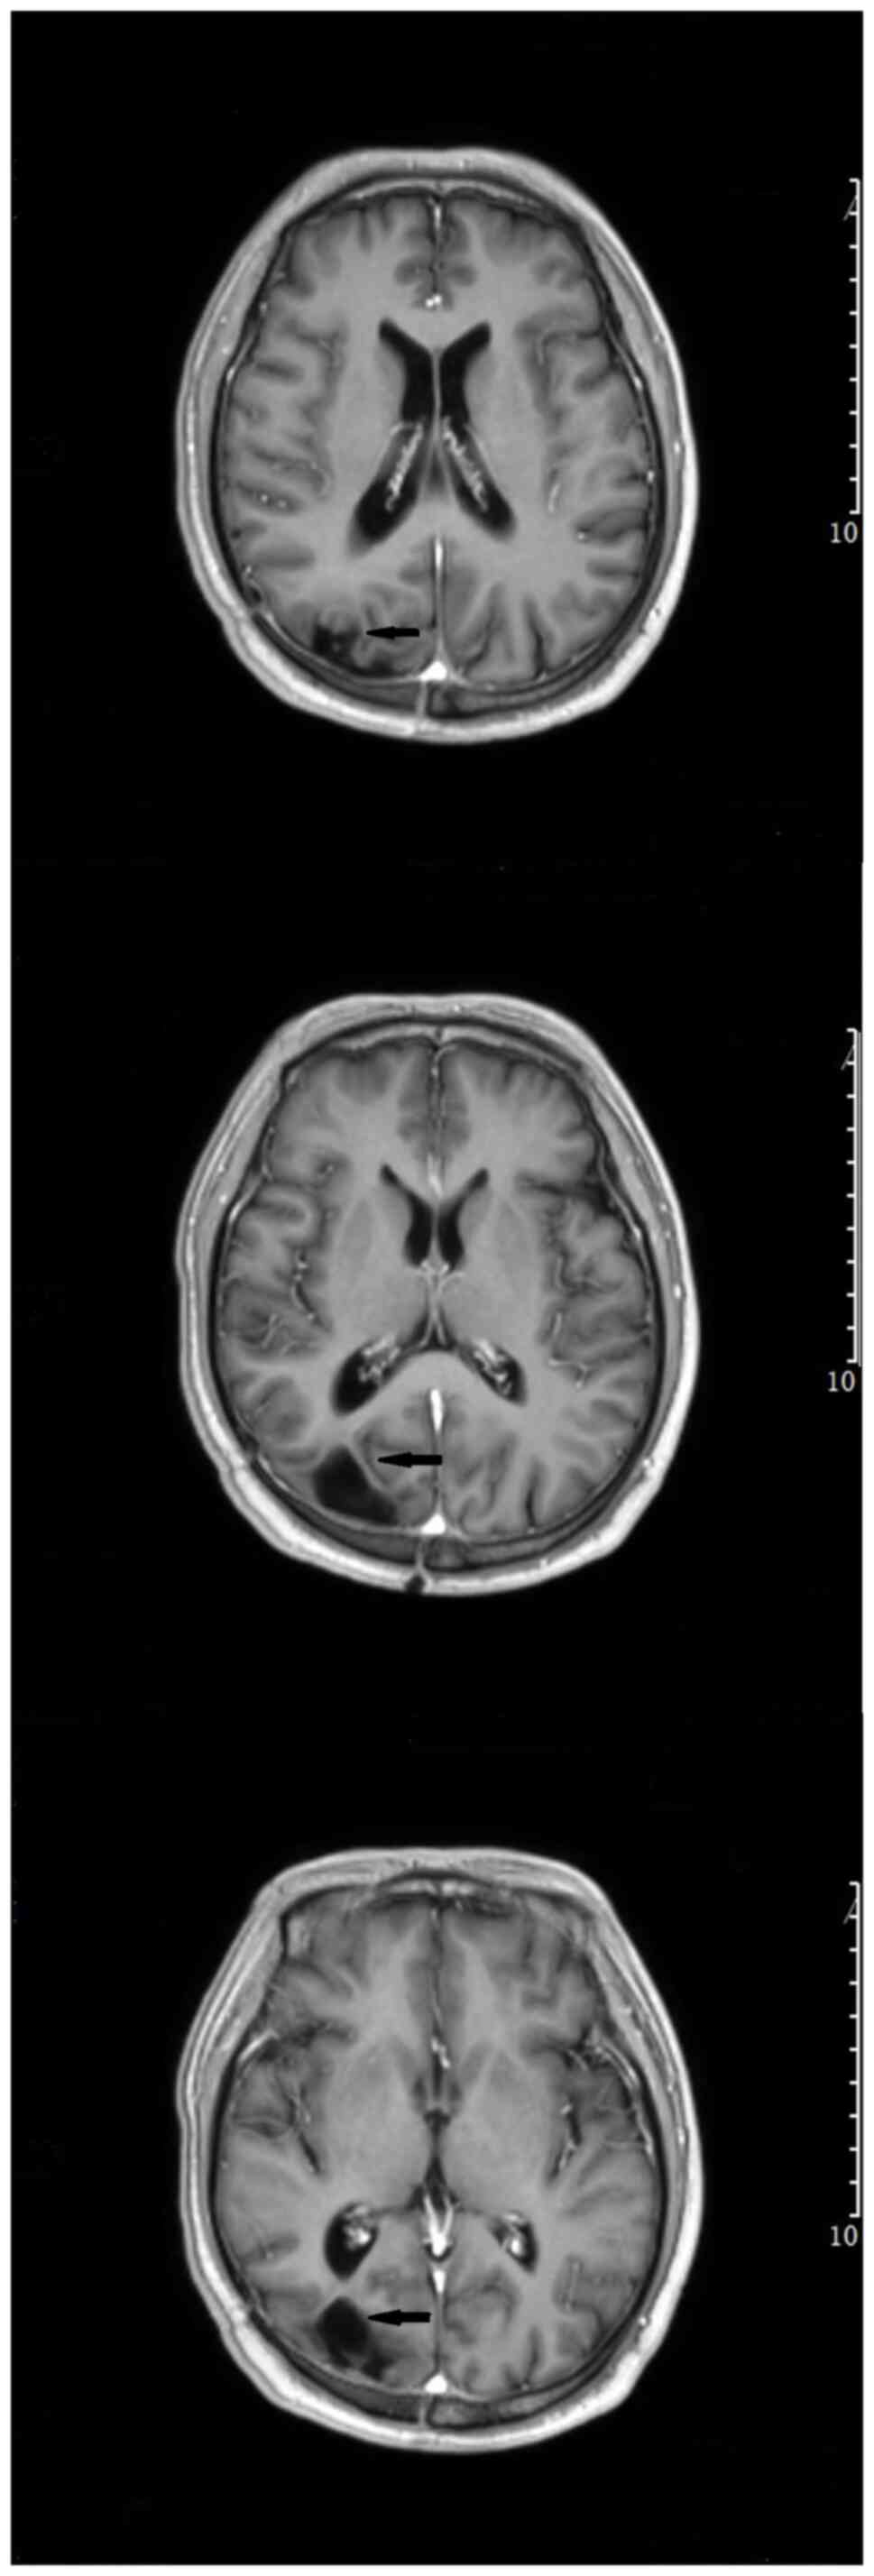

After being treated with voriconazole (0.2 g; Q12 h) for two straight weeks, the patient recovered well, with the body temperature back to normal range. The follow-up CT brain imaging results were also found satisfactory (Fig. 4). Since the patient required further chemotherapy, he was referred to the hematology department of The First People's Hospital of Huzhou for further anti-infective therapy. Voriconazole was used for intensive treatment (0.2 g; Q12 h) in the first 3 months. Following that, the patient's temperature was normal and his condition was generally stable and the patient has now entered maintenance treatment (0.1 g; Q12 h). No additional PCR or NGS tests were performed following surgery, cerebrospinal fluid test and enhanced head MRI were reviewed in June 13, 2023. Fortunately, the patient's head MRI (enhanced T1) showed no obvious enhancement of the disease (Fig. 5). There was no increase in micrototal protein (Pyrogallol red colorimetry) and no decrease in sugar content in cerebrospinal fluid test, suggesting that there was no abnormal index of cerebrospinal fluid infection. Although it cannot be ruled out that the patient has a recessive Aspergillus infection, treatment is still effective at the time of writing. In the later stage, the authors recommend that patients undergo NGS testing of cerebrospinal fluid to further determine whether there is a recurrence of Aspergillus.

Figure 4

Head computed tomography examination after operation showed satisfactory results. The arrows in the images indicate the operating area. Most of the lesions were resected without postoperative bleeding.